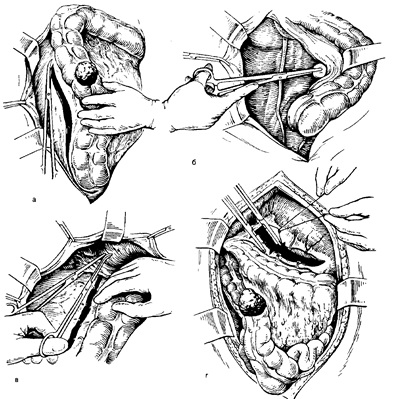

Működés: széles medián laparotomiát. Termé-DYT felülvizsgálatát a hasüregbe. Ütemezett térfogata művelet természetétől függően és a közös-ség a kóros folyamatot. Hurkok a vékonybél-meghajtót a bal fele a hasüregbe és a otgorazhi-vayut steril törölköző, mártott meleg-isotopy nikai nátrium-klorid oldattal. A mozgósítása a jobb felét a vastagbél, kiindulva az ileocekális szög, elfog 10-15 cm alatti vzdoshnoy belekben. Erre a célra, a vakbél és a felszálló vastagbél visszahúzzuk befelé és vonuljon 1,5-2 cm Knara Ms a vakbélig kivesszük ollóval hátsó pas rietalnuyu hashártya végig a jobb oldalcsatornás, pro-szekcionált Folytatva a ileocekális szög a külső széle a vakok és felszálló vastagbél, hogy a jobb kanyar (ábra. 12a). Ahhoz, hogy megkönnyítse a boncolás a hashártya, a „a korábban beadott egész 0,25% novocain oldat mennyiségben 100-120 ml. Géz vattacsomót a bilincs nyersen elválasztjuk mediálisan vakok és colon ascendens a bélfodor (ábra. 12b). Így a hátsó hasfal (retroperitonealis), látható mediálisan lefelé, és az alsó vízszintes része duodenális Kish-Ki és oldalsó - jobb ureter, amely körül valamennyi manipulációk végrehajtásához szükséges egy nagy-vanced PICs hogy nem károsodott. Vérző erek lekötjük. További mozgósítani jobb hajlító obodoch-sósav bél és jobb harmada. Ehhez apránként NE-metsző befogóelemek közötti hepatocelluláris szalag és ligáltuk selyem (ábra. 12c). Csak kötőszöveti vezetékek metszik a duodenum és a hátsó felület a jobb hajlítása a vastagbél egy kötelező ligációs selyem hajó. Ha a hajlítás a jobb elosztása szükséges óvatos, hogy ne sértse meg a fejét a hasnyálmirigy és a Poggio ludochno-nyombél artériát, ami tönkreteheti a vérellátás on-nyombélben.

Ezután, a pofák közötti és töredékes keresztmetszete ne revyazyvayut selyem gasztrointesztinális keresztszalag pro-vontatási 7-8 cm-re a kanyarban a jobb szintjének eltávolítását a jobb harmadában a haránt vastagbélben (ábra. 12 g). Cseplesz eltávolítjuk szintje szerint Rezek-TION keresztirányú vastagbél ligációs selyemmel hajók (összes cseplesz vákuumban eltávolítjuk, a rák).

Pere-részén bélfodor kezdődik terminalis ileum szegmenst el kell távolítani. Erre a célra, bizonyos távolságra a 10-15 cm-re a vakbél, tompa műszere-MENT (Kocher clamp), közelebb a belekben, a csípőbélben mesenteriumban csinál egy lyuk; rajta elvégzett ragasztva gumiból vagy gézzel, amely emelje fel a bélben, és ettől a ponttól felé vakbél ileum bélfodor cross-órás tyam között a szorítókat és ligáltuk selyem.

Ezt követően, egy asszisztens, két kézzel emeli fel a vakbél és a jobb hajlítása a vastagbél és a bélfodra a vastagbél # 1218; yagivaetsya, amely megkönnyíti a határokon. Bélfodor, etetés a jobb fele a vastagbél hajók - vastagbél iliaca artériát és a jobb vastagbél, a kísérő véna és jobb oldali ág a középső kólika artéria - külön kereszt között a szorítókat és ligáltuk selyem (12. ábra, d.). A központi végén az artériák biztonságosabb kötni a két öltés. Bélfodra levágni túlzott zhimah, amennyire csak lehetséges a bélből, hogy távolítsa el a nyirokcsomók a lehető retroperitonealis zsír, ami különösen fontos a rák.

Ábra. 12. Jobb oldali hemicolectomy. Műveleti lépésekben.

és - vágás a hátsó parietális hashártya a vakbél jobbra az első kanyarban;

b - Tanszék vak colon ascendens az ő média-line (alján a seb látható húgyúti Točník); in - a kereszteződés hepatocelluláris ínszalag; g - a kereszteződés gasztrointesztinális ínszalag; d - vágás a belső réteg Bry-zheyki vastagbél (NE-kereszteződés helyeken csípőbélben és keresztirányú vastagbél-set mondta példány: 1 - A jobb oldali ág közepén kólika artéria; 2 - Jobb kólika artéria; 3 - vastagbél csípőartériába.

Amikor hemicolectomy a rák mondta tartályokkal ajánlatos kötni hossz-SRI művelet elején, mielőtt mozgósítja-CIÓ bél megelőzésére metastazirova-CIÓ kezelése során; ugyanerre a célra ajánlott gézkötés bélben két csík 3-4 cm felett és alatt a daganat. A fő szár középső vastagbél artéria nem metszi egymást, és kizárólag a ligálást és kereszteződés csak a kisebb ágakat elérte a nagy-üvöltve fele a vastagbélben. Csak abban az esetben, maxi-mal mozgósítása a keresztirányú vastagbél, hogy a bal oldali harmadik vagy több (pl, a rák-harmadát jobbra) elkötöttük és a határon a középső kólika artériát.

Eltávolítása előtt a jobb fele a vastagbél hasüreg elkeríteni nagy géz hagyva részei, amelyet csökkenteni a bélben. Az elején a kereszt keretében mozgósított-vzdoshnoy belekben. Erre a pre-pro-bél Shiva tűzőgép, vagy a kereszt vonalat részek egymásra az egészséges bél bilincsek (soft-Cue - a fennmaradó rész, kemény, - a kilépő része), amelyek között át a bélben. Továbbá, közötti bél bilincsek, mobilizálni kereszt-nek a jobb harmadában a haránt vastagbélben. Távolítsuk el az összes mozgósított a jobb felét a vastagbél együtt a terminális szegmens (10-15 cm) az ileum. A végén a vastagbél és a vékonybél kezeltük 3% alkohol oldat jód és 0,02% -os vizes klór-hexidin géz és zárt.